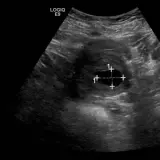

Over 2,100 interactive radiology cases, curated by radiologists for your level of training. Scroll, window, and view cases full screen โ€” just like on PACS. Click linked findings in each writeup to jump straight to them on the image. Cases include sample reports, a focused discussion section, original illustrations, and videos.

Casi completamente interattivi con gli strumenti che ti aspetti su un PACS: scroll, windowing, zoom, pan, misurazioni, ROI e modalitร  a schermo intero.

Annotazioni dettagliate evidenziano i reperti chiave direttamente sui casi. Clicca sui reperti collegati nella descrizione del caso per saltare alla loro esatta posizione sullo scan.

Studia in modo efficiente con reperti di imaging annotati e illustrazioni